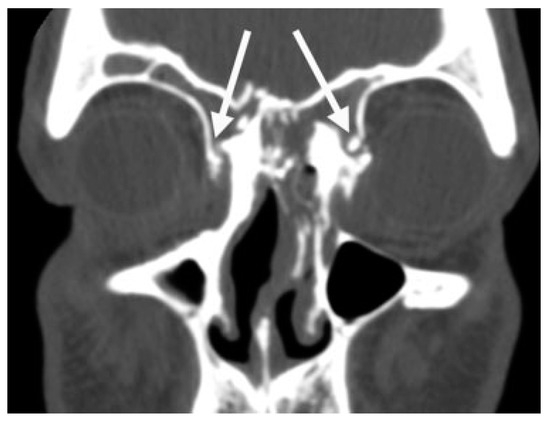

A thin-cut (1.0 to 1.5 mm) axial, coronal, and sagittal computed tomography (CT) scan is the radiological gold standard for diagnosis of frontal sinus fractures. Axial images provide the best information about the anterior and posterior tables (Figure 2); coronal images are used to assess the sinus floor and orbital roof (Figure 3). Sagittal reconstructions can be useful in assessing the patency of the frontal recess (Figure 4), and three-dimensional recon- structions may help to visualize the external contour deformity seen less clearly with two-dimensional cuts alone (Figure 5).

Figure 3.

Coronal computed tomography scan demonstrat- ing disruption of the medial orbit and frontal recess (arrows).